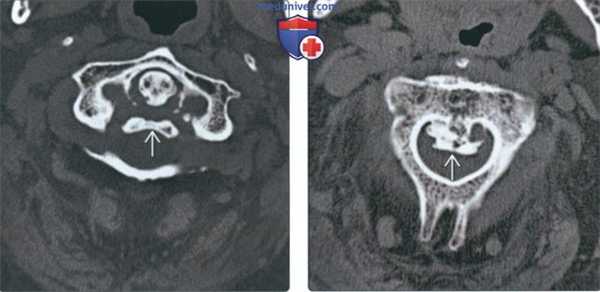

(Слева) На аксиальной КТ в костном окне определяется ОЗПС в сочетании с ДИСГ. В самых верхних отделах ОЗПС выглядит как пальцевидное выбухание, обычно не контактирующее с позвонком.

(Справа) На аксиальной КТ в костном окне определяется выраженная оссификация ЗПС в основании С2, сливающейся с задней кортикальной плааинкой позвонка. Результирующее сужение позвоночного канала приводит к тяжелому сдавлению спинного мозга и симптомам миелопатии, наличие которых является одним из немногих показаний к хирургическому вмешательству.